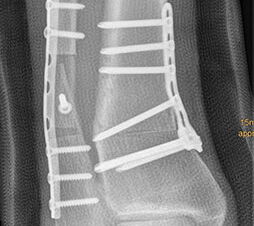

Auch hier wird die Korrektur im CORA (Center oft Rotation and Angulation) durchgeführt. Primär werden intraoperativ unter Bildwandler Kontrolle Kirschner Drähte als Sägelehre konvergierend eingebracht. Dann wird der geplante medialbasige Keil mit der oszillierenden Säge entfernt. Die laterale Kortikalis sollte geschont werden, sie dient als Drehpunkt für die Osteotomie. Die Osteosynthese kann dann im Sinne einer Zuggurtung ein besonders stabiles Konstrukt bilden. Liegen mehrdimensionale Deformitäten vor, die eine Korrektur in Translations- und Rotationsebene erfordern, ist eine Durchtrennung der lateralen Kortikalis notwendig, ebenso bei ausgedehnten Korrekturen mit Keilhöhen über 10mm 218.

Wir benutzen zur Osteosynthese 3,5 mm LCP T-Platten. In der intraoperativen Röntgenkontrolle kann im seitlichen Bild die Zentrierung des Talus überprüft werden, und ggf. durch eine milde extendierende oder flektierende Korrekturkomponente verbessert werden 18. Eine begleitende Deformität der Fibula korrigieren wir üblicherweise mit einer z-förmigen Osteotomie die wir mit einem 1/3 Rohrplättchen sowie einer Zugschraube sichern 18.